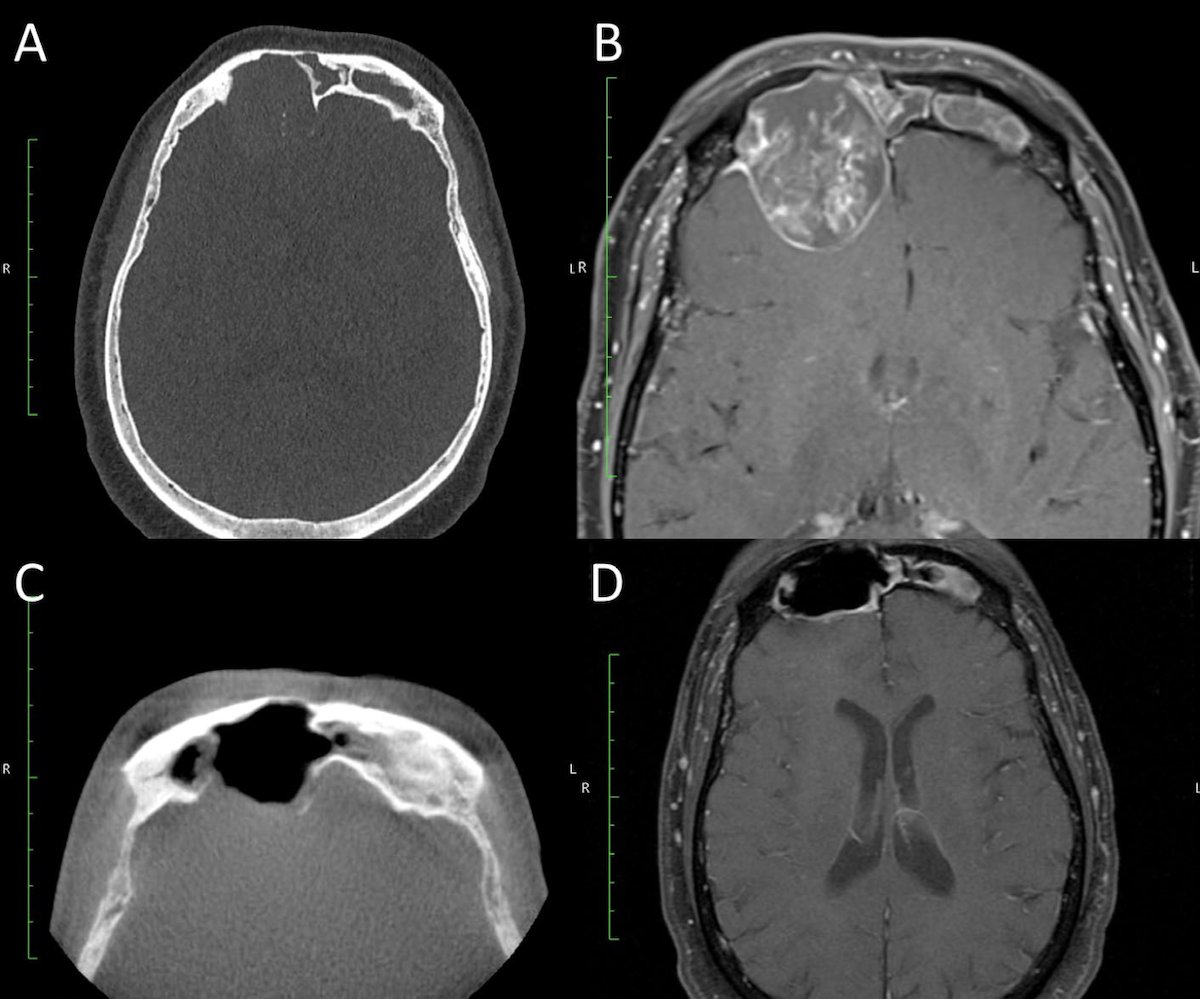

What are the surgical challenges and outcomes of treating frontal sinus inverted papilloma, a tumor often linked to skull base involvement and recurrence?